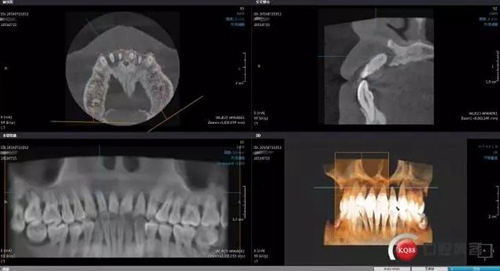

GBR術(shù)后CBCT

接下來是GBR五個(gè)月后CBCT,當(dāng)然(1-5月)中間也有拍全景,不一一展示了。

成骨效果尚可,進(jìn)行手術(shù)